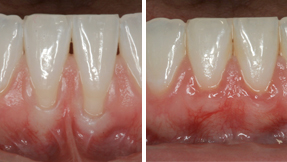

Gum Recession Correct the look of a receding gum-line

Receding gums are a very common dental problem. Gum recession is a condition where the gum line pulls away or becomes unattached from the tooth exposing the tooth root. Often, gum recession is referred to as being "long in the tooth". This process unfortunately is accompanied with bone loss and can contribute to tooth loss.

Gum Grafts (Gingival Grafts)

Microsurgery is an ideal solution when treating gum recession because the use of the microscope provides both precision as well as an esthetically pleasing outcome. It differs from a skin graft in that a traditional skin graft leaves an open wound in the roof of the mouth (palate), often painful, and does not cover the exposed root. The color match on a skin graft is often less than ideal. Whereas a microsurgical graft transplants a thin piece of connective tissue gently removed from under the palatal skin. The skin is closed and heals with minimal discomfort. The graft is precisely placed under the gum and over the exposed roots. The microsurgical graft is inherently esthetic by design and accomplishes predictable root coverage and periodontal health.